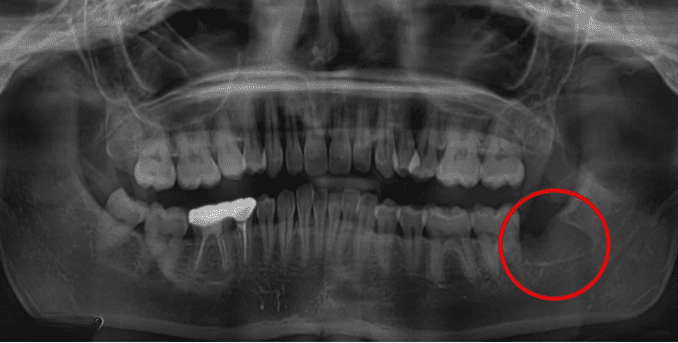

Wisdom Tooth Removal-2

Wisdom Tooth Removal-1

Examination & X-ray

Dentist evaluates position of tooth and surrounding structures.